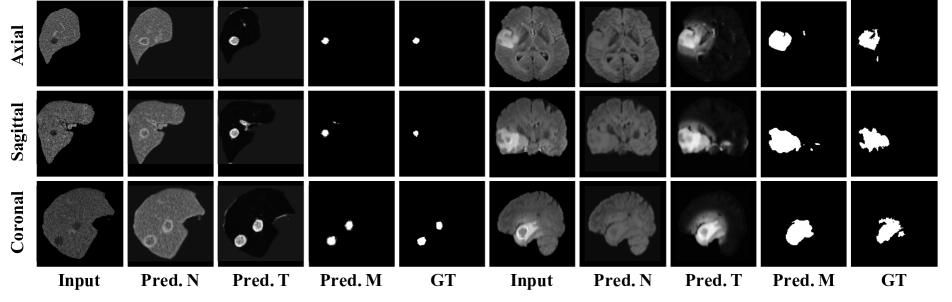

5.2 Comparison on Zero-shot Tumor Segmentation

In this section, we compare with state-of-the-art unsupervised anomaly detection methods. As shown in Table 3, our approach surpasses the other ones by a large margin, in particular, on brain tumor segmentation (WTS), we substantially improve the Dice score over the recent state-of-the-art methods from to , and from to on liver tumor segmentation (LTS). In Figure 4, we show qualitative results from our self-supervised model on real tumor data under a zero-shot setting, i.e. models are directly adopted for mask prediction without using any manual annotation whatsoever. As can be seen, our method accurately detects and segments the tumors, along with the intensity distribution of the restored image closely resembling that of the normal organ, effectively inpainting the tumor regions. However, note that we do not favor high-quality reconstructions, what we really care about is the tumor segmentation mask. More visualisation can be found in the supplementary material.